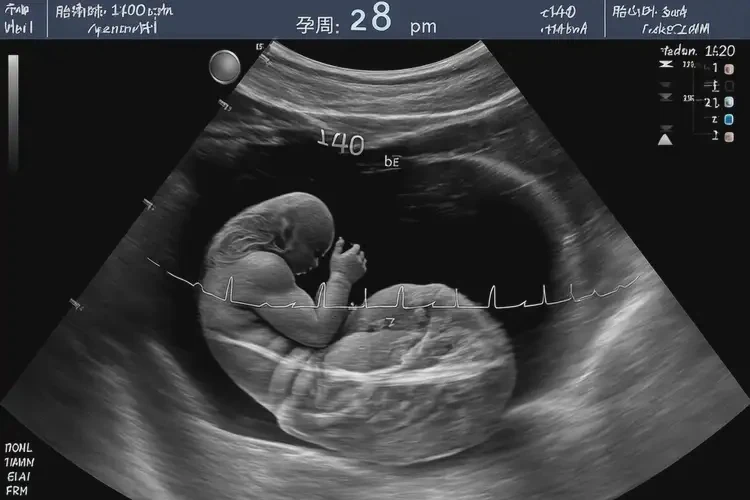

孕39周5天胎心100多寶寶還能要嗎(圖1)

• 超聲檢查:通過超聲檢查評(píng)估胎兒的發(fā)育情況胎盤功能以及是否存在其他異常。